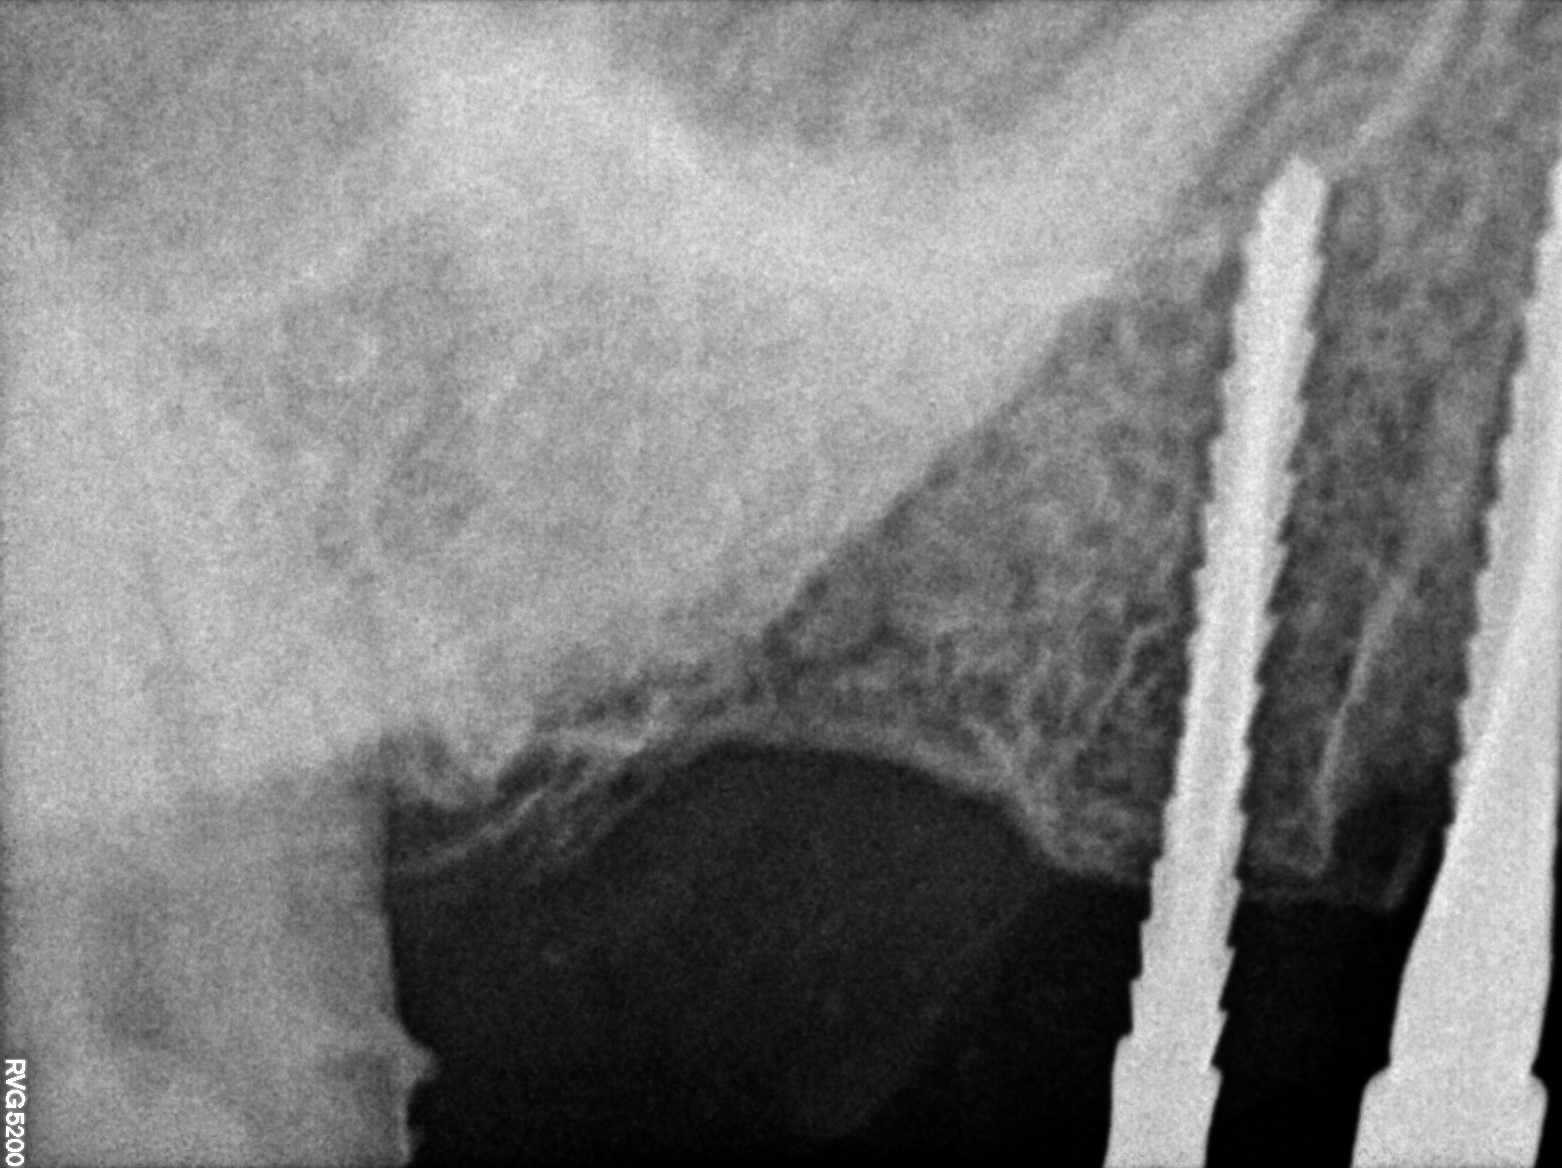

Dental Radiographs FHIR: DocumentReference · LOINC 24641-7

R71.jpg

24641-7

| Dental implant placement | 234781005 | D6010 Surgical placement of implant body | ##44, #45, #47 | 2023-03-13 | completed | abutment placed 44 & 45 & 47 | |

| Dental implant placement | 234781005 | D6010 Surgical placement of implant body | ##44, #45, #47, #75, #11, #14, #15 | 2022-11-25 | completed | implant placed & 44 & 45 & 47-3-75*11-5 & t-30 & 14--4-2*10 & 15--3-75*10 & t-10 | |

| Dental implant placement | 234781005 | D6010 Surgical placement of implant body | — | 2022-08-04 | completed | abutment placed | |